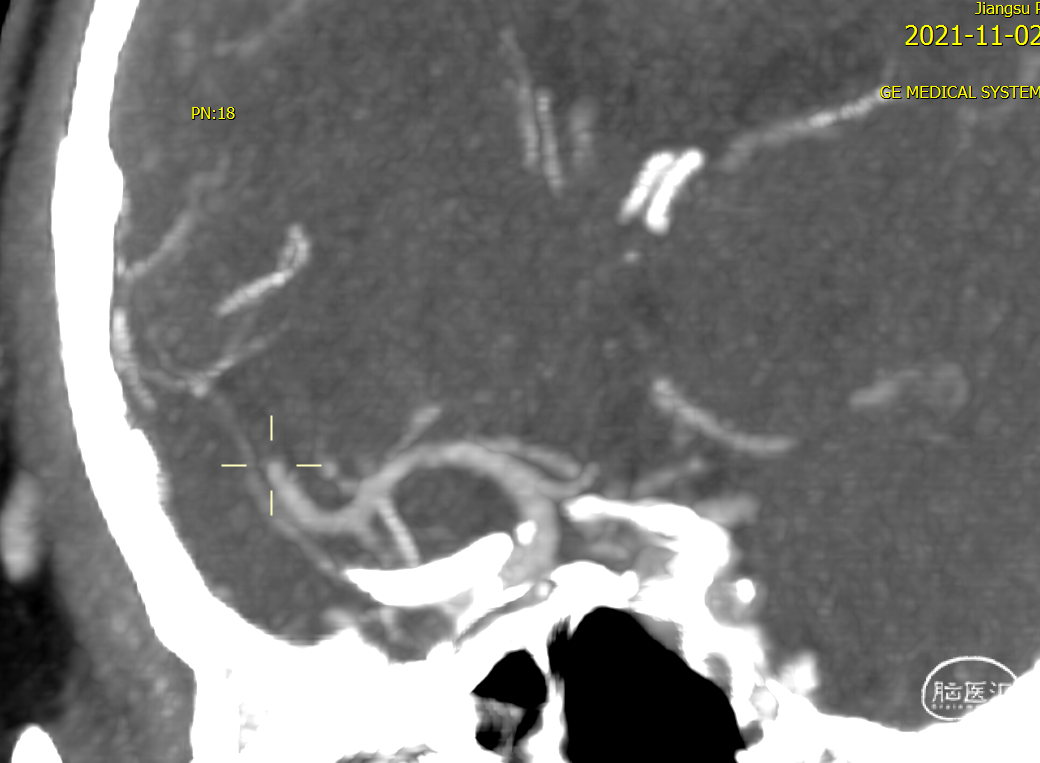

术前CTA提示右侧大脑中动脉M2段闭塞

右侧大脑中动脉上干闭塞(M2),影像评估机械取栓,抽拉结合,M2 位置较远,器械选择关键